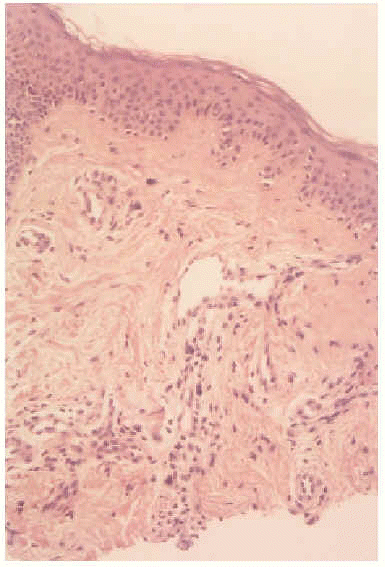

Una mujer de 22 años acudió a la consulta por lesiones cutáneas asintomáticas de 3 años de evolución. Presentaba telangiectasias que afectaban a la zona maxilar inferior y lóbulo del pabellón auricular izquierdos, y no desaparecían ni a la vitropresión ni a la digitopresión (fig. 1). La anatomía patológica mostró una epidermis de aspecto normal. En la dermis, la estructura del colágeno no mostraba anomalías, y se observaban capilares dilatados con monocapa de endotelio de aspecto ortotópico, sin infiltrado inflamatorio acompañante en dermis media (fig. 2). La inmunohistoquímica para receptores de estrógenos y progestágenos fue negativa.

Fig. 2.--Vasos dilatados con endotelio de aspecto normal.